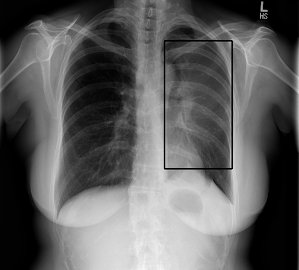

Inteligencia artificial aplicada a imágenes, ya sean de bases de datos existentes o generadas en tiempo real, hacemos implementaciones de modelos con cámaras y otros periféricos para la captura de patrones en el mundo real y la automatización de respuestas.

Para lo que no se pueda resolver con análisis matemático tradicional, podemos hacer uso de redes neuronales convolucionales y recursivas. Efectuamos el proceso de ingeniería de caracteristicas para el entrenamiento de la arquitectura de red neuronal modelada especialmente según se requiera.